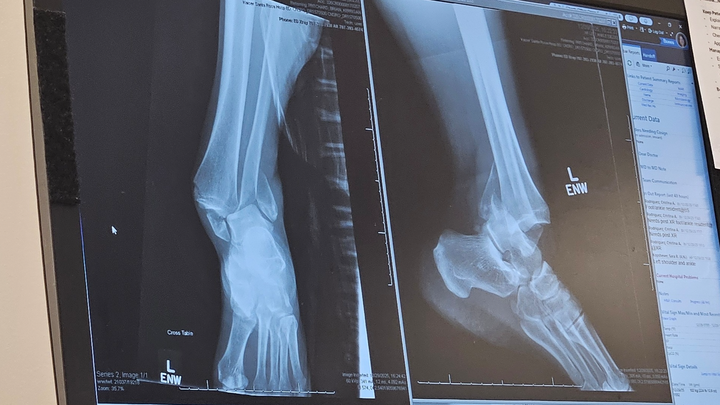

Over Christmas break, my kids and I took a short family adventure to San Francisco—grateful for time together, laughter, and making memories. Just a few days later, on Monday, December 29th, while roller skating with family at our local rink, I experienced a sudden and freak accident that resulted in a severe ankle injury.

I stayed calm, and thankfully my family was there to help care for the kids while paramedics transported me by ambulance to the hospital. I spent the day in the ER, where I was placed in a soft cast and sent home with pain medication while awaiting surgery.

Surgery took place on January 2nd. Since then, recovery has been more challenging than expected. I am currently non-weight-bearing on my left ankle and must remain mostly flat with my leg elevated while my body heals. Pain management has been difficult, and day-to-day tasks require support.